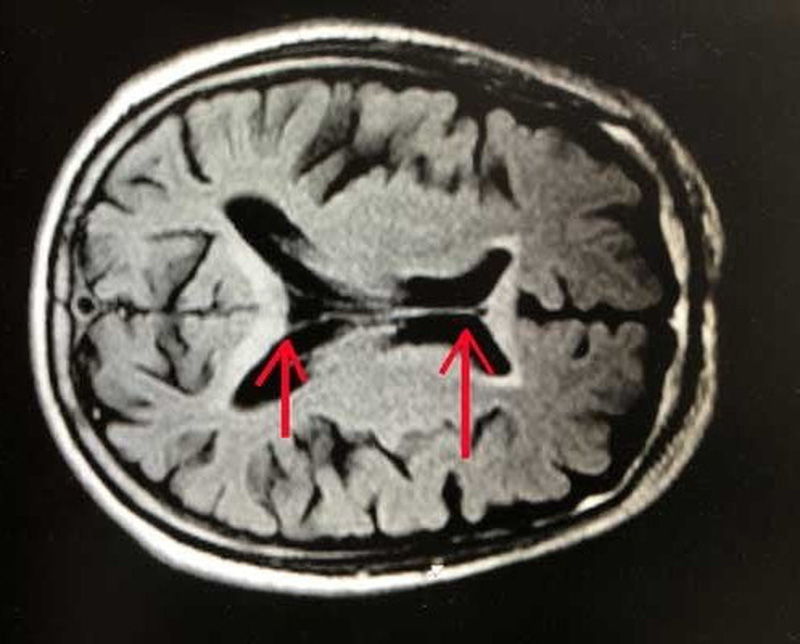

Sau khi tiến hành thăm khám, khai thác bệnh sử các bác sĩ chẩn đoán bệnh nhân mắc bệnh Marchiafava Bignami. Đây là một thể bệnh tổn thương não do sử dụng rượu và chưa có thuốc điều trị đặc hiệu…

Theo các bác sĩ, bệnh Marchiafava Bignami được mô tả vào năm 1903 bởi Marchiafava và Bignami, hay gặp ở bệnh nhân nghiện rượu, đặc trưng là tổn thương hủy Myelin và hoại tử ở thể chai. Có thể gặp tổn thương các sợi liên hợp bán cầu hay chất trắng đại não.